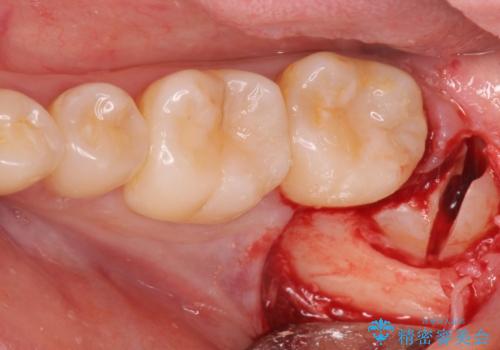

- 左下親知らずが腫れてる感じがして痛いとの事で来院。

抜歯を希望されたので抜歯術を行いました。

- 外科手術のため、術後に出血、痛みや腫れ、違和感を伴います